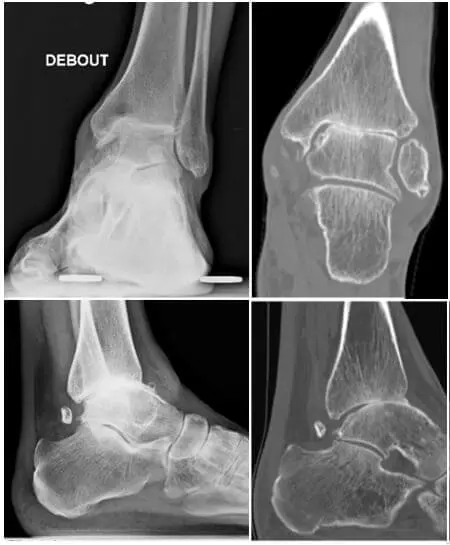

Osteoarthritis can be defined as the presence of degenerative lesions, wear and local or generalized reduction and/or loss of cartilage at the level of a joint. Several mechanical causes may lead to this: repeated sprains, instability, experienced fractures, osteochondral injuries… On radiographs, we can see an asymmetric narrowing of the joint space, a condensation of the underlying bone, formation of bone growth, cyst formation,….

In case of arthritis, there is a more homogeneous destruction of the cartilage, by, often, autoimmune disorders such as rheumatoid arthritis, psoriasis,… This almost always means that the capsule is weaker and of lower quality as a result of which it is sometimes difficult to preserve the mobility of the joint. A choice must then be made between an increased risk of recurrence versus performing an arthrodesis. On radiographs, the joint space is more symmetrically affected.